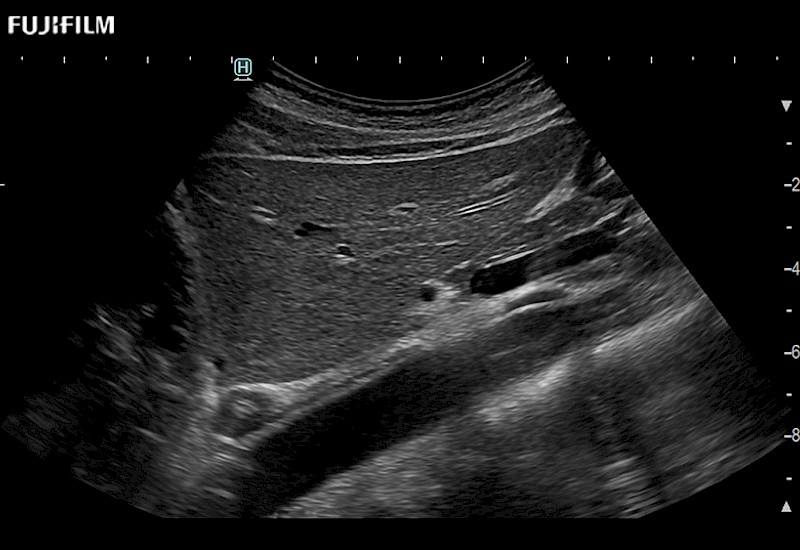

Extraordinary high-resolution digital imaging

- Exceptional near and far-field resolution

- Instant feedback on tumor margin delineation

- Ideal for liver and kidney scanning

- Exceptional near and far-field resolution

- Instant feedback on tumor margin delineation

- Ideal for liver and kidney scanning

- Exceptional near and far-field resolution

- Instant feedback on tumor margin delineation

- Ideal for liver and kidney scanning

- Exceptional near and far-field resolution

- Instant feedback on tumor margin delineation

- Ideal for liver and kidney scanning

- Exceptional near and far field resolution

- Instant feedback on tumor margin delineation